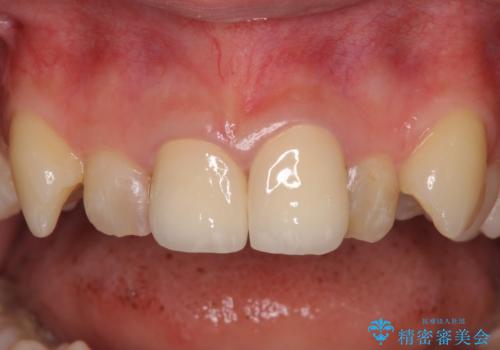

上の奥歯は金属色が見えることもないため、審美的な問題は全くありません。